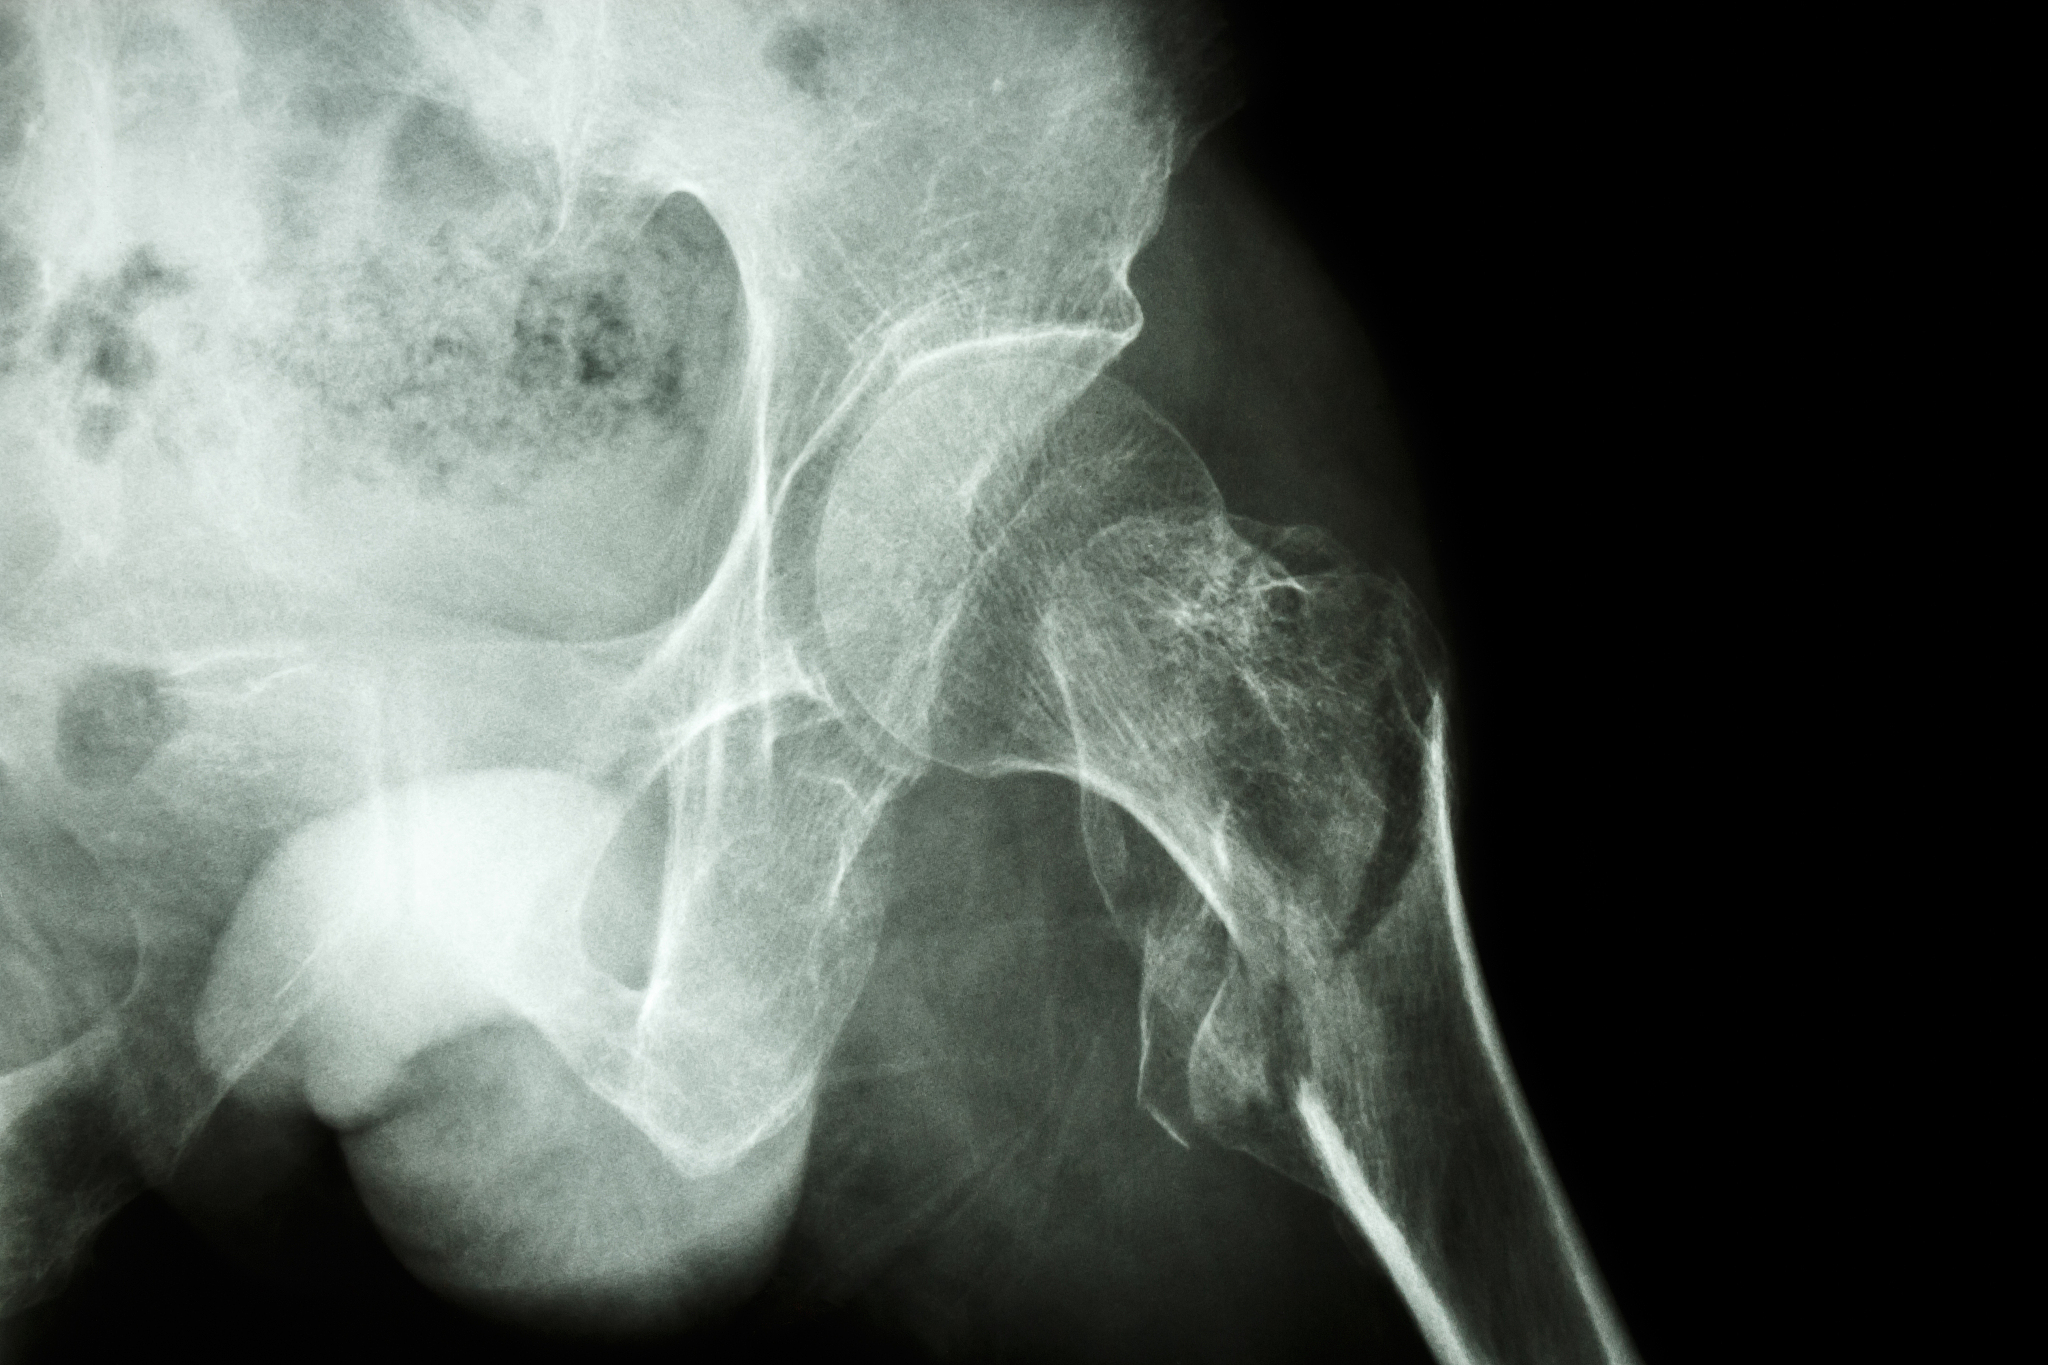

3. 骨质疏松:骨质疏松是股骨粗隆间骨折的主要原因之一,患者骨密度降低,骨质变脆,容易发生骨折。

高龄股骨粗隆间骨折:老年患者自身风险因素分析